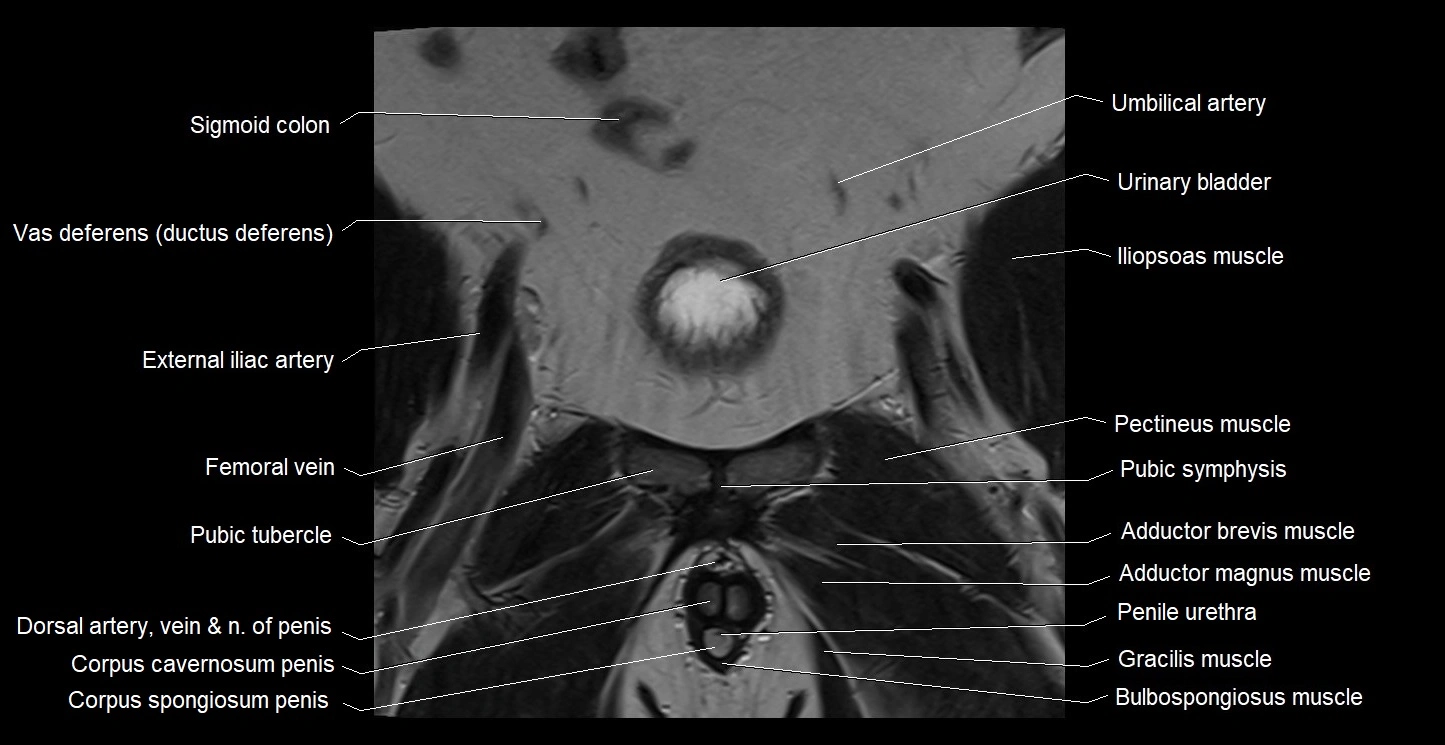

- Bulbospongiosus muscle (Male)

- External iliac artery

- Femoral vein

- Gracilis muscle

- Penile urethra

- Pubic symphysis

- Pubic tubercle

- Sigmoid colon

- Umbilical artery

- Urinary bladder

- Vas deferens